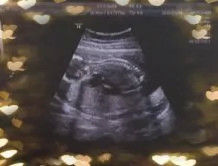

第14周,妈妈去做了B超,这是妈妈第一次看到你,你像一个小茄子,那么小,那么可爱,大夫说:“这个小家伙一点都不老实,像在蹦极。”妈妈还听到你坚实有力的心跳,那一刻,妈妈又哭了。

这是你在妈妈肚子里14周-36周的变化,妈妈悄悄把它记录下来了。